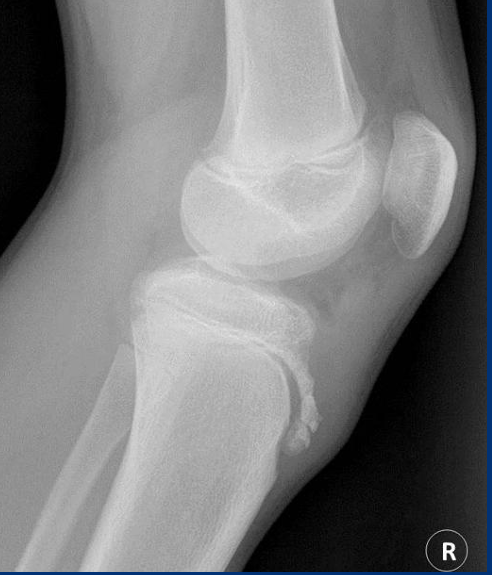

Classification - Osgood Schlatter’s

inflammatory

can be traumatic

Etiology - Osgood Schlatter’s

repetitive strain

commonly seen in active teens

Pathogenesis - Osgood Schlatter’s

traction force of the patellar tendon causes inflammation and fragmentation of the immature tibia

Rad - Osgood Schlatter’s

ST swelling

loss of sharp patellar tendon margins

tibial tub fragmentation